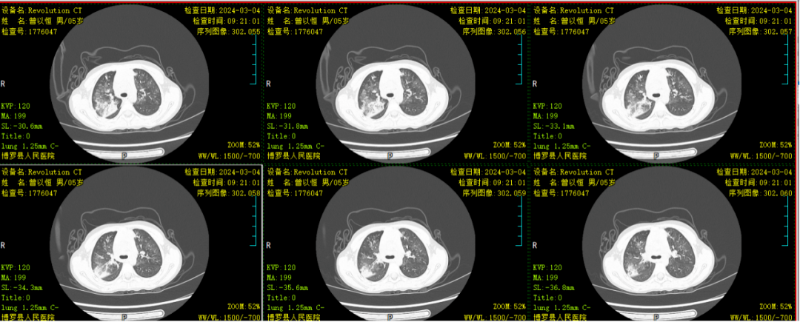

文章配圖

△復查胸部CT示:病灶較前明顯吸收。

結合胸部CT特點,符合行電子支氣管鏡檢查指征,予行肺泡灌洗治療。肺泡灌洗液送檢提示肺炎支原體感染,予加用阿奇霉素抗感染治療。行電子支氣管鏡肺泡灌洗治療一周后,患兒無發熱,咳嗽較前明顯好轉,聽診肺部無啰音,復查胸部CT顯示病灶較前明顯吸收,予帶藥出院。